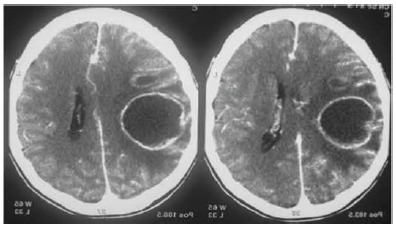

Com base nesse caso hipotético, assinale a alternativa que apresenta as características esperadas quanto à intensidade do sinal hemático nas ponderações T1 e T2, respectivamente.